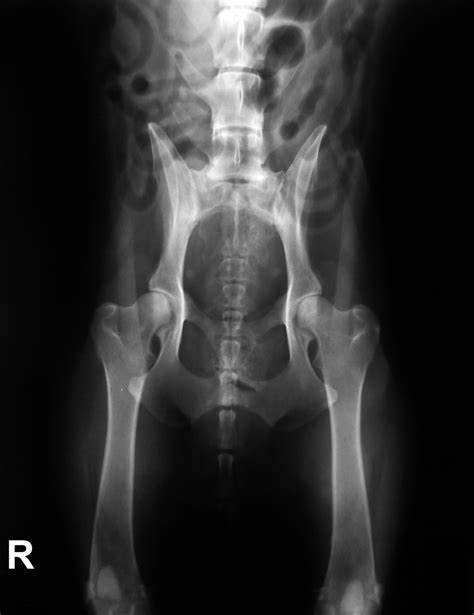

Diagnostika dysplázie zvyčajne zahŕňa röntgenové vyšetrenie, ktoré sa vykonáva v anestézii. Narkóza je nevyhnutná na uvoľnenie svalov a zabezpečenie správnej polohy pre snímkovanie. Veterinárny lekár môže pomocou röntgenových snímkov vyhodnotiť závažnosť dysplázie a posúdiť zmeny v kĺbe.

Zásadným hodnotiacim kritériom pri DBK je „Norbergov uhol“. U psa bez DBK by mal byť uhol väčší ako 105 stupňov. Ďalšími znakmi dysplázie sú sploštenie kĺbovej jamky alebo hlavice stehennej kosti, vychýlenie krčka alebo hlavice stehennej kosti a príznaky artrózy.